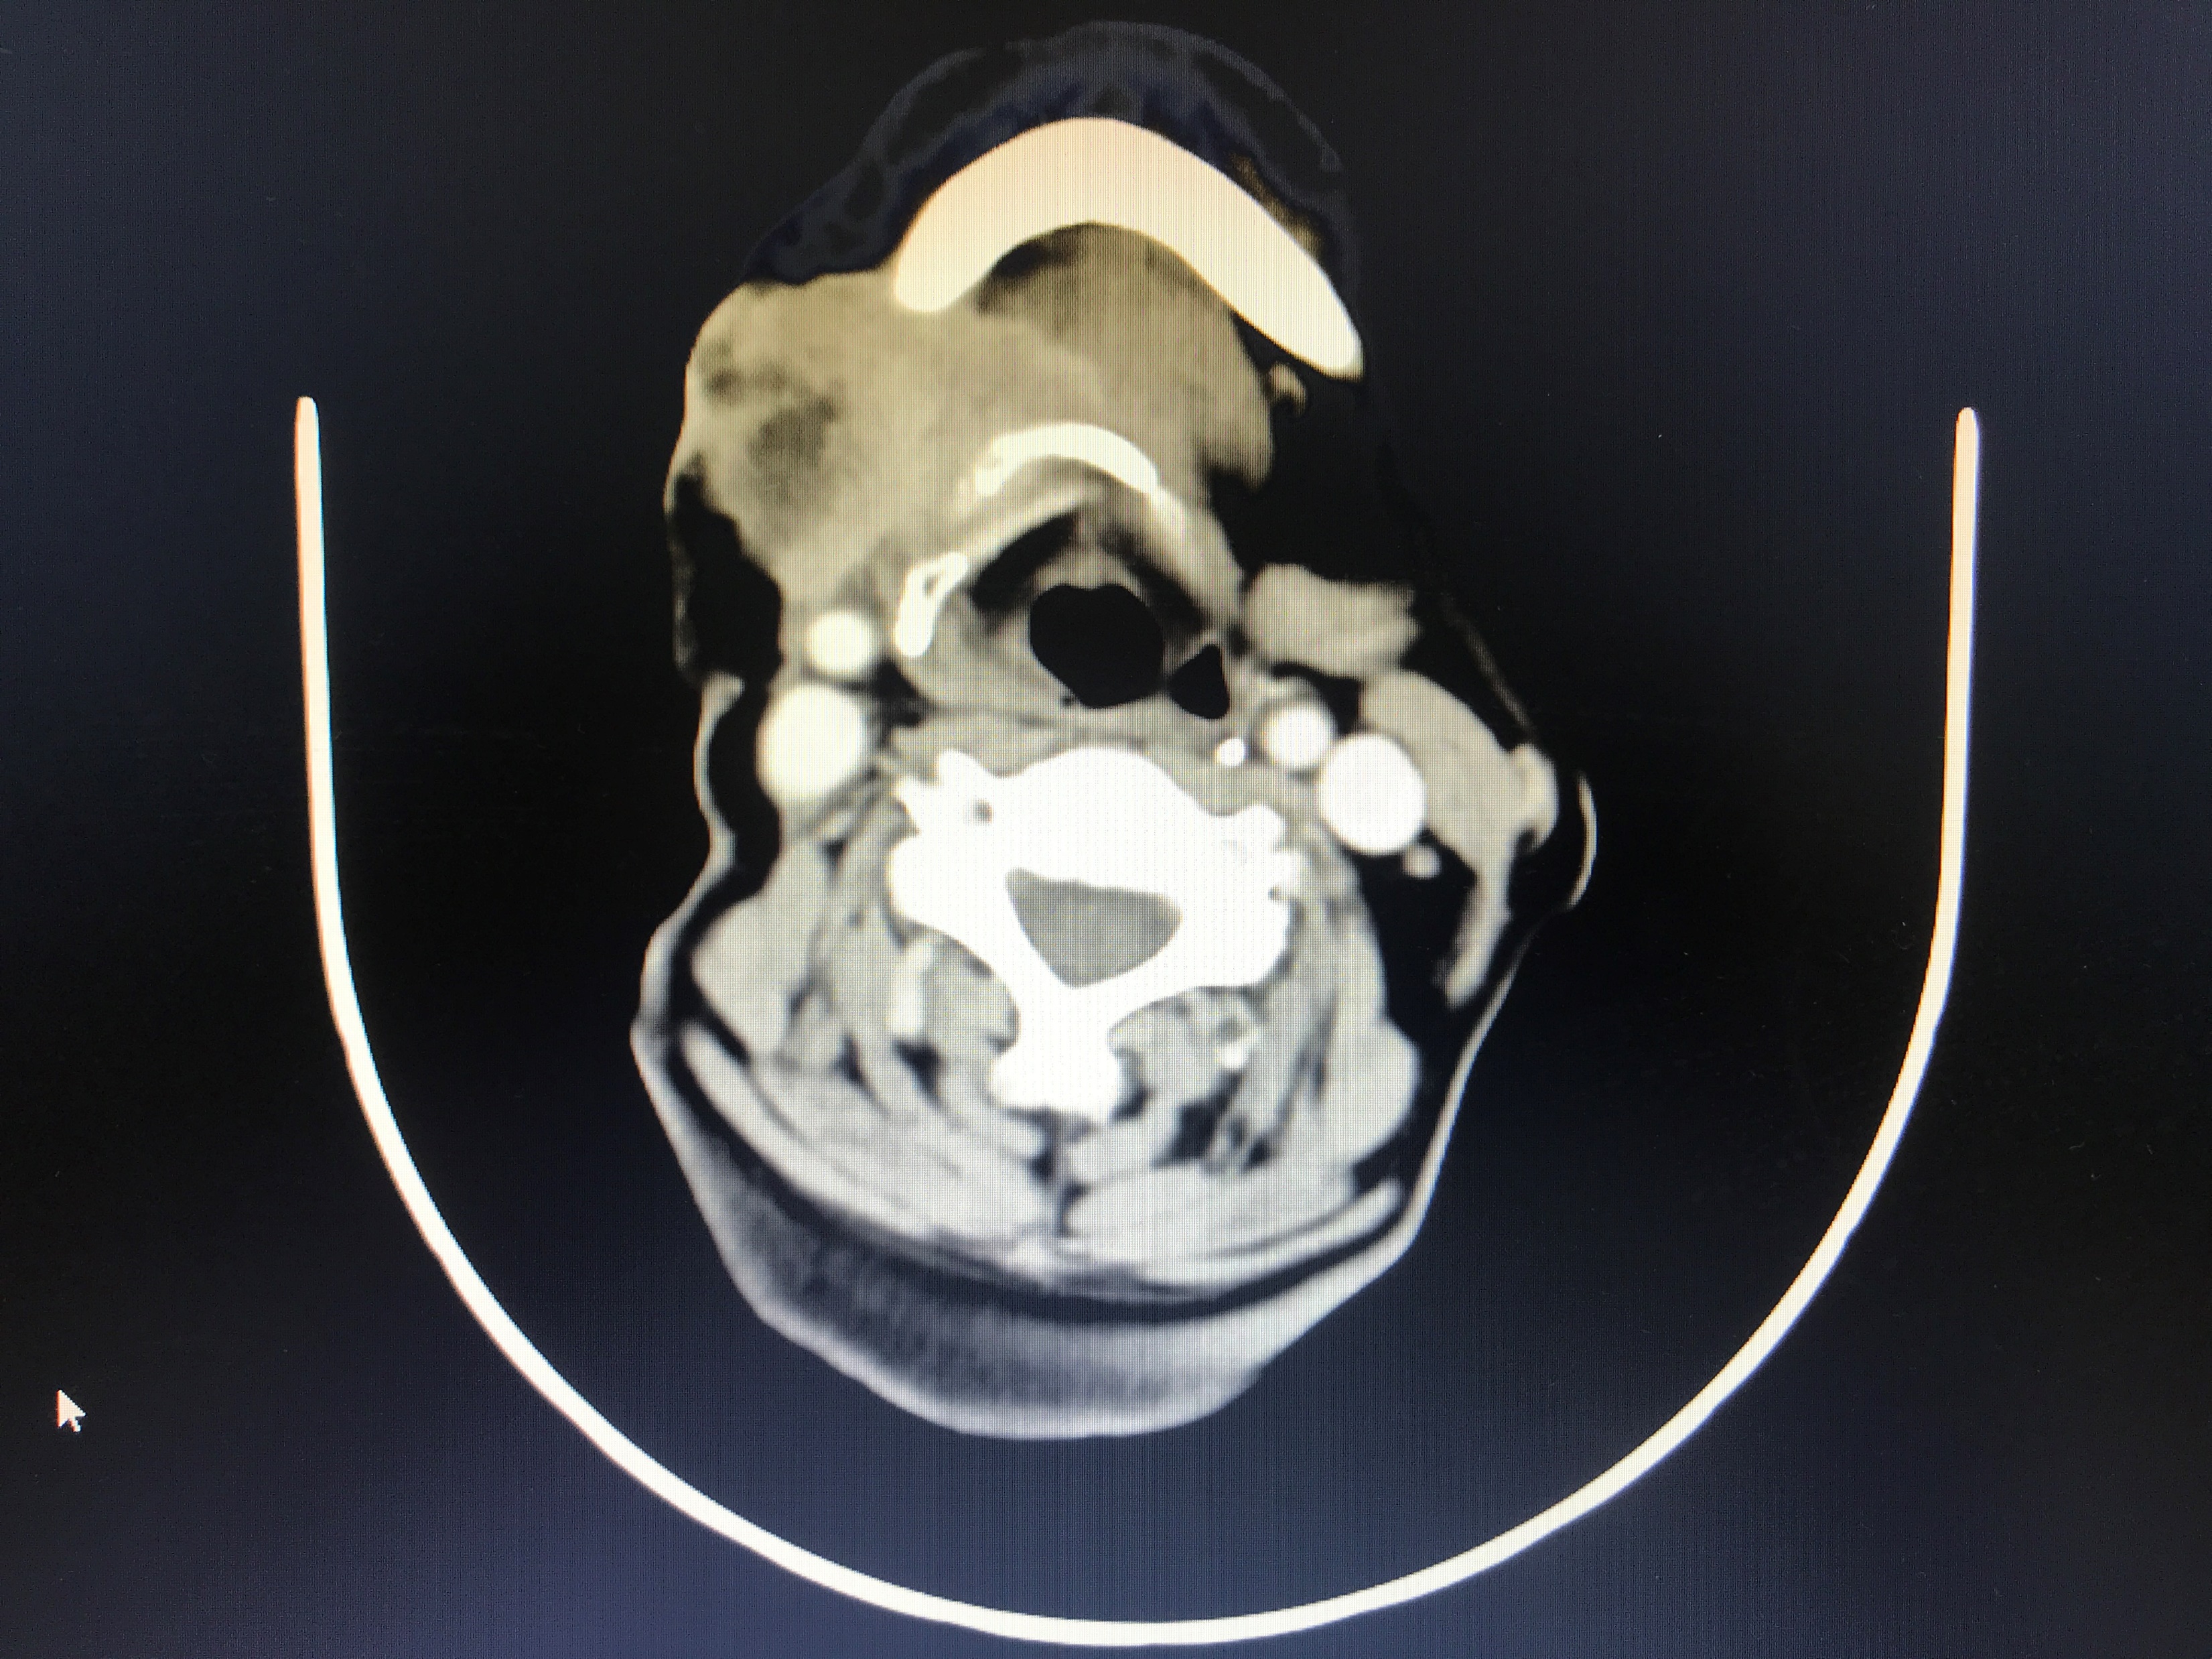

患者65岁,5年前确诊为“右舌鳞癌”并进行手术,今年年初因出现右颌下区复发,受疫情影响,未能及时就医,出现肿瘤增大并局部皮肤破溃症状,CT提示肿瘤包绕右下颌骨,并侵犯右侧口底,与右颈总动脉关系密切。

我院头颈外科收治患者后,经过检查并初步认为,患者复发肿瘤侵犯范围较广,手术需要将颌下区受累的皮肤、右下颌骨、右侧半舌及口底组织连同转移癌一并切除,形成颌面部洞穿性缺损,颈部皮肤缺损,因颈内静脉及颈动脉的分支切除,且难以再行游离皮瓣修复。为克服这个难题,头颈外科团队为患者精心设计了手术方案,采用胸大肌皮瓣修复,将右侧胸大肌皮瓣分成三个部分,分别修复口底缺损,面部缺损及颈部缺损。这种“一瓣三补”的手术方案,完美地解决了术后修复及功能重建,为这例复发晚期的头颈部鳞癌患者再次迎来生机。